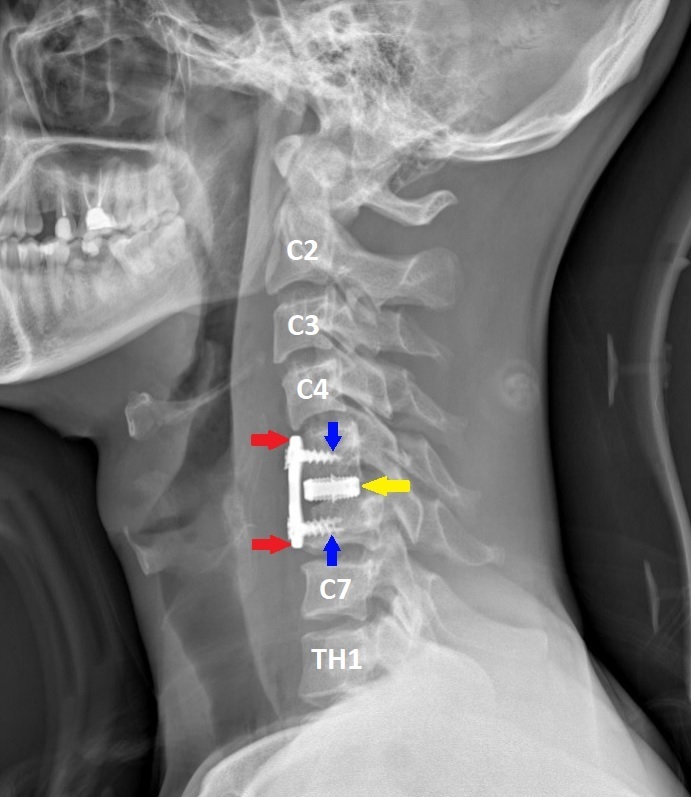

Операцию проводили хирурги Петр Галкин и Михаил Ветров. Под увеличением, с использованием операционного микроскопа, через небольшой разрез кожи по передне-боковой поверхности шеи была удалена травматическая грыжа диска. Затем под рентген-контролем был успешно вправлен вывих, а позвонки зафиксированы при помощи титановой пластины и пластикового кейджа между позвонками.

На следующий день после операции пациенту уже разрешили вставить и ходить в жестко фиксирующем шею воротнике. Контрольное обследование на третий день показало, что все функции организма удалось сохранить, имплант надежно фиксирован, а шов отлично затягивается, рассказал заведующий нейрохирургическим отделением Владимир Сериков. Пациента выписали на 5-й день после операции.